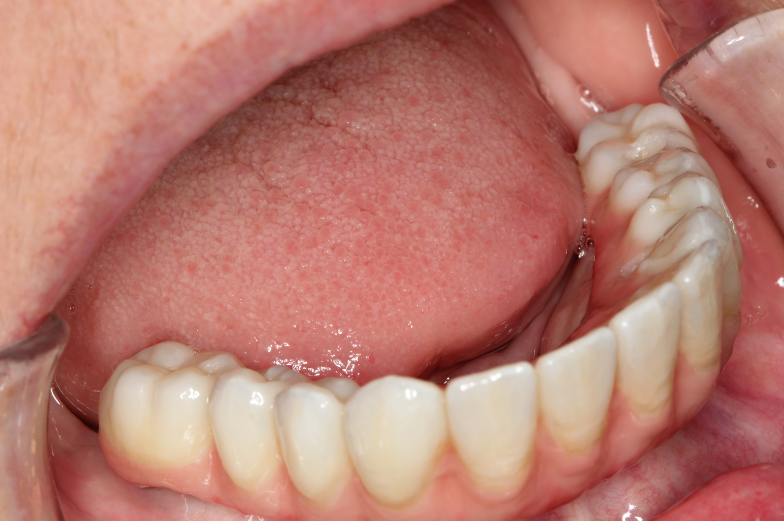

CHECK OUT THIS AWESOME RESULTS

(use cursor to move arrows left and right to see before and after images)

Posterior screw retained implants